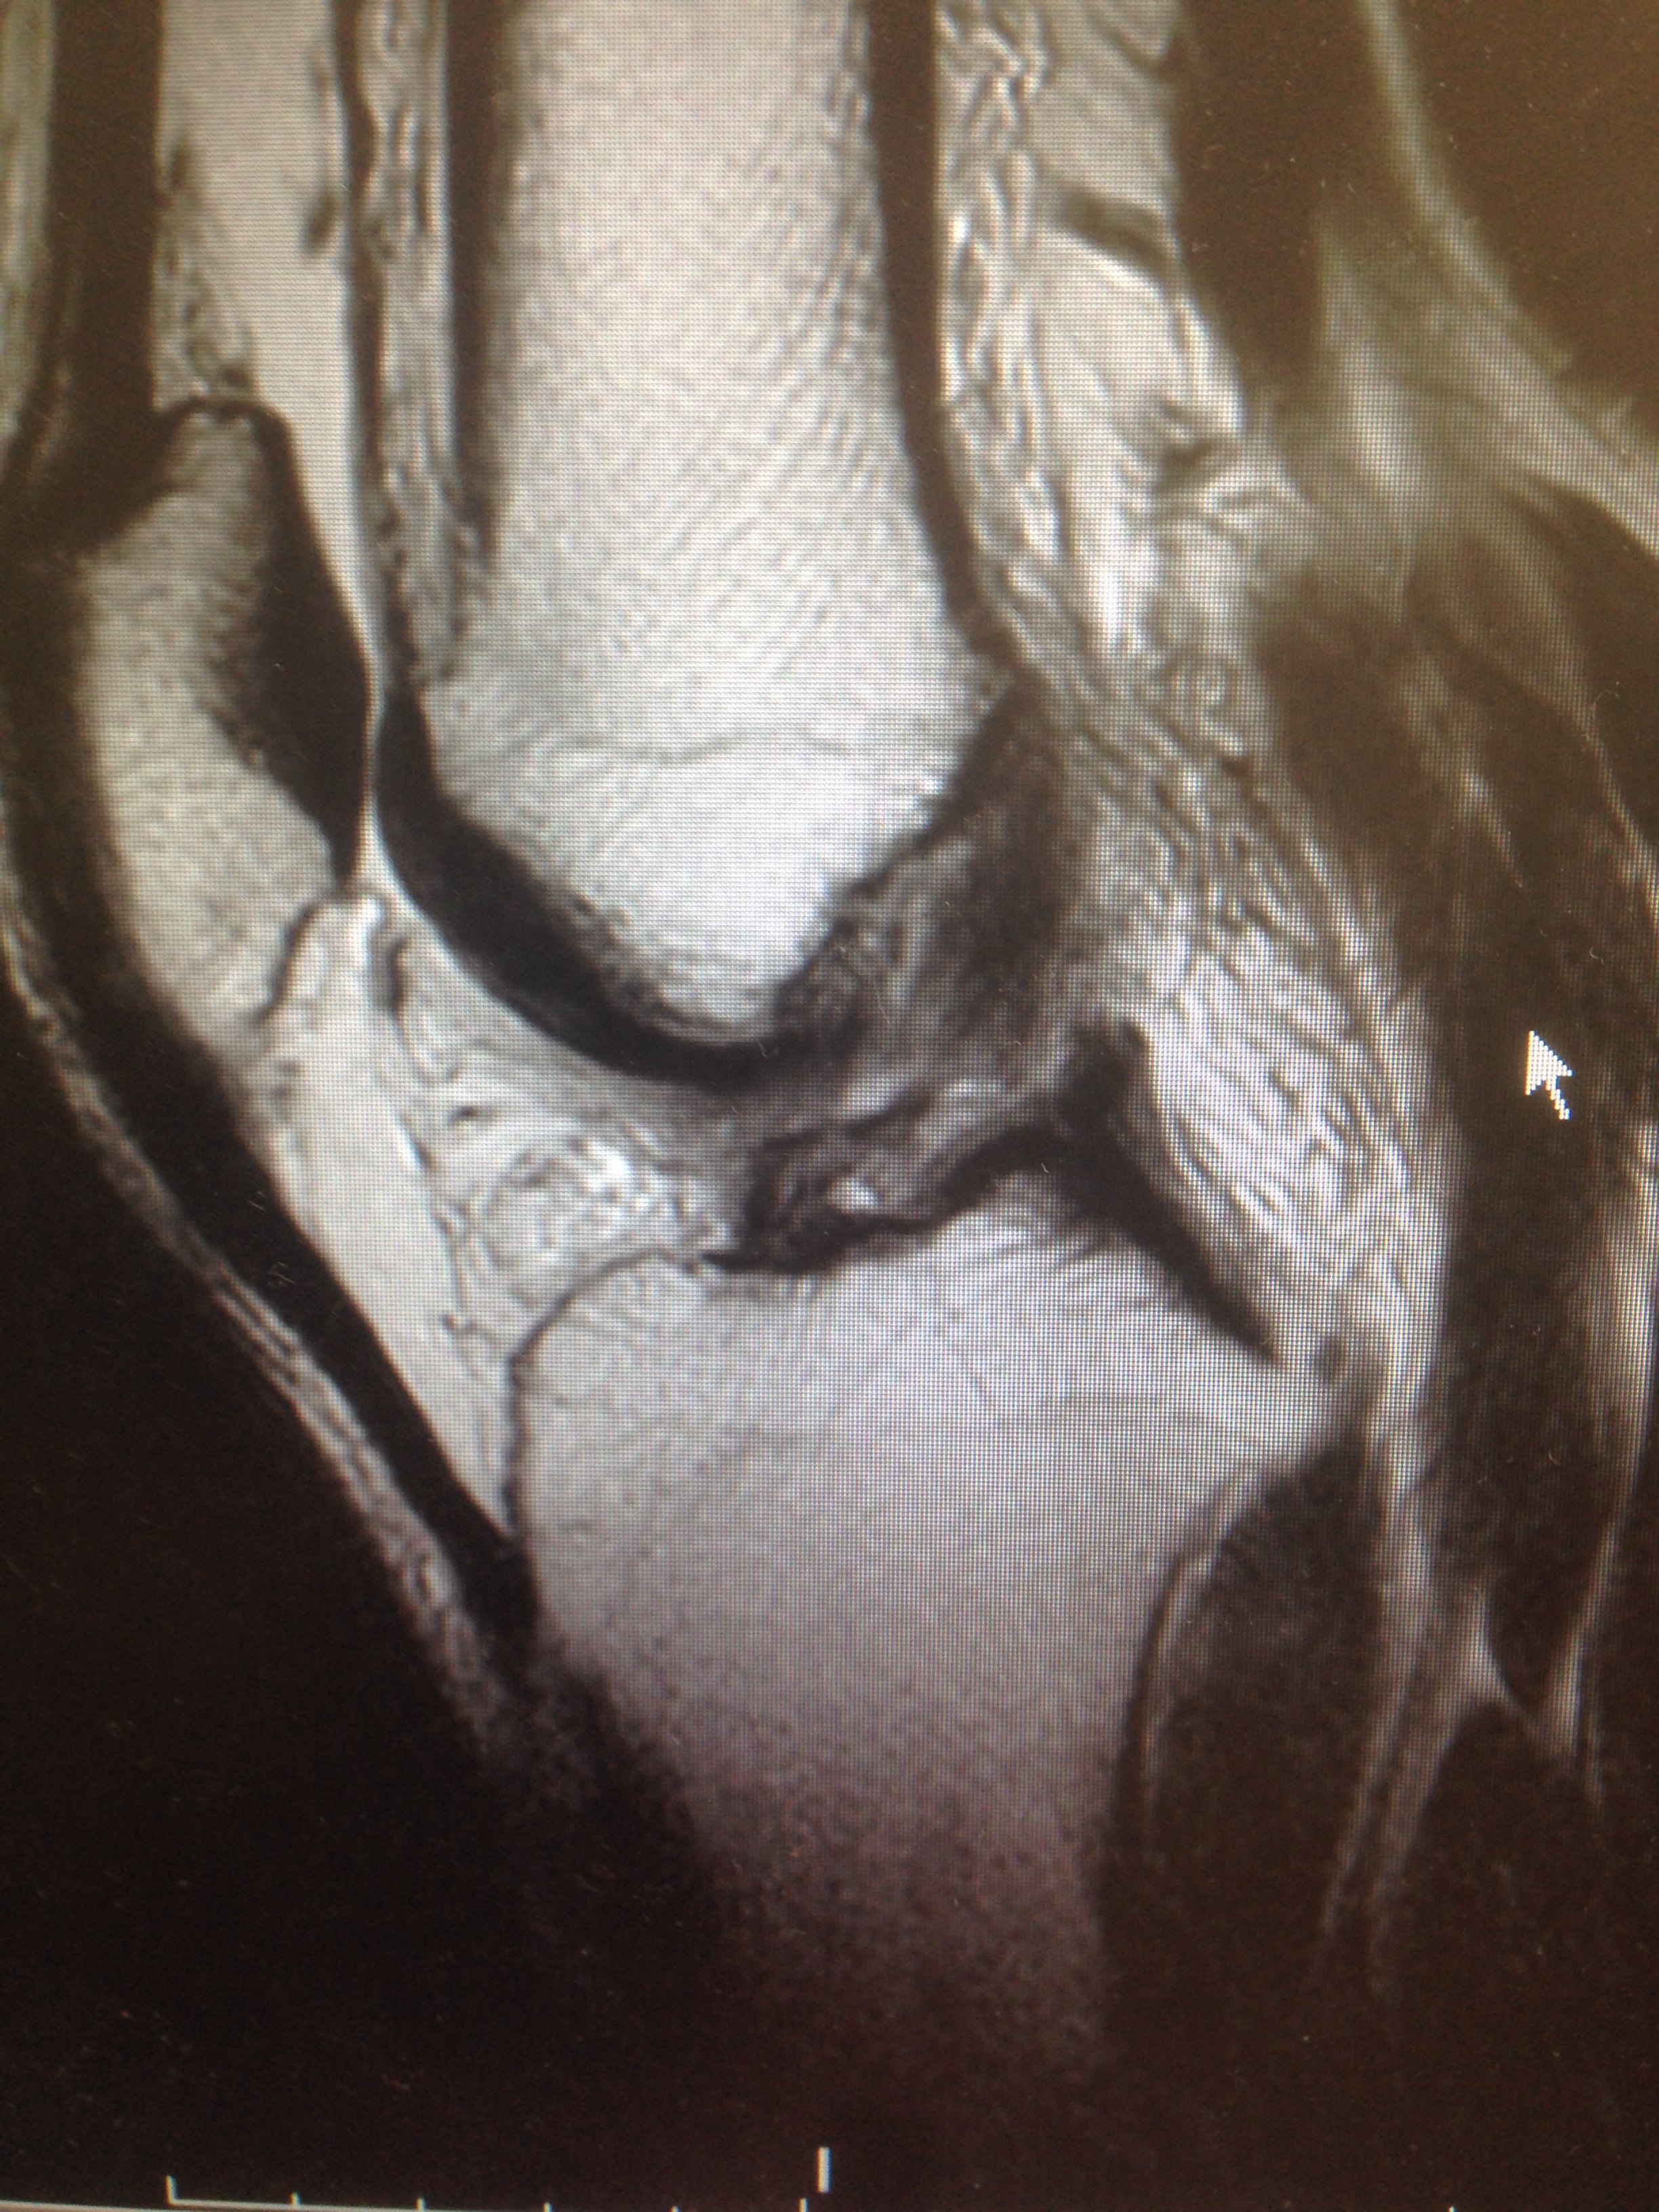

ちなみに内側(小指側)が痛いものは「上腕骨内上顆炎」といいます。 膝が痛い 膝の痛みには、事故やスポーツ外傷などで急に発生するもの、運動のやりすぎによるもの、中年以降慢性的に起きてくるものがあります。 外傷による障害の代表的なものとして半月板損傷、靱帯の損傷があげられます。上記の画像は膝の骨挫傷(こつざしょう)を MRI撮影したものです。 こちらのサイトを参考にしてみてください。 ↓↓↓ Medical Note「MRI画像あり骨挫傷とは?症状や診断、治療まとめ!」 転倒や捻挫などの原因がない関節の痛みは要注意! 今回、私の右足首の骨挫傷(こつざしょう)は日本大百科全書(ニッポニカ) 骨挫傷の用語解説 骨折しているのではなく、骨の内部が損傷している状態をいい、出血や炎症および強い痛みを伴う。打撲や転倒などの衝突によって外部から鈍的な圧力が加わった場合におこり、手指の中手骨や膝(しつ)関節および足関節の外傷などの際によくみられ

12 骨挫傷および半月板損傷 特定医療法人 同心会 遠山病院